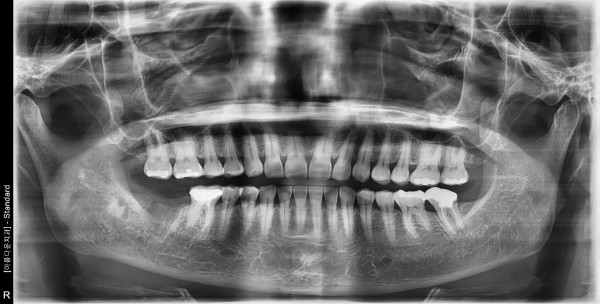

56세 여자 하악 구치부 뼈 이식후 임플란트 식립